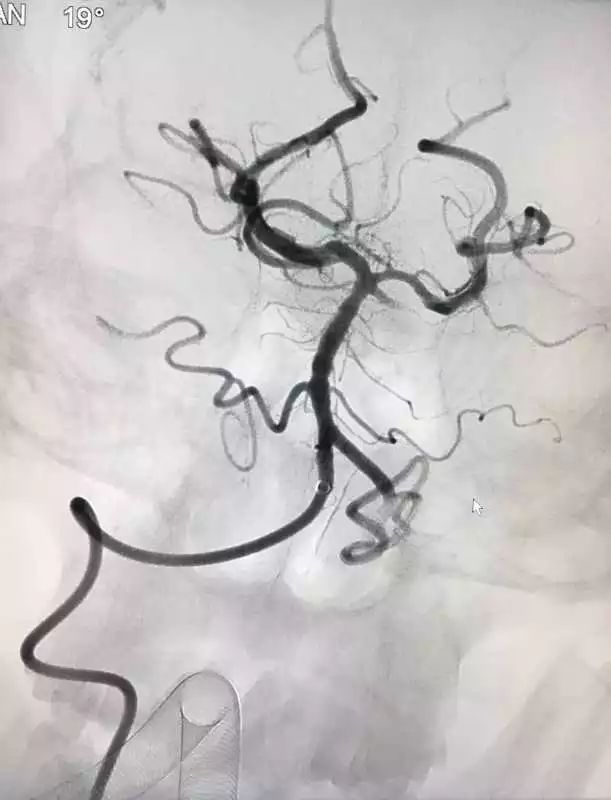

脑血管造影(dsa)显示该病灶为脑动静脉瘘.

取栓后全脑血管造影

脑血管造影

血管造影

脑血管造影术